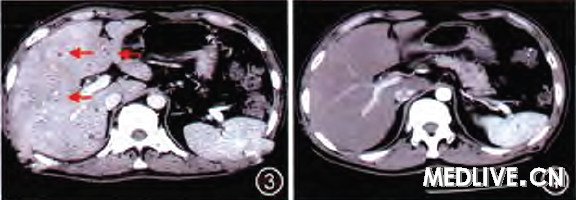

入院后给予抗感染(头孢地嗪)、护肝(还原型谷胱甘肽)、退热 (双氯芬酸钠栓)营养支持等处理;连续3 d患者精神较差,体温仍高,最高达40.5℃,高热时头痛明显、伴四肢乏力,应用退热栓后可控制数小时,曾解黑色大便1次,量不多尚成形;彩色B超示:肝脏体积增大,内可见多个大小不等低回声光团,提示肝内多发实质性占位(肝癌可能):增强CT示:肝内多发性占位,考虑为肝寄生虫病及肝脏肿瘤(图1)。

2周后患者精神逐步好转,大便转黄,肝区叩痛消失,仍间断发热。复查上腹部CT示肝内多发低密度影范围较前缩小,病灶周围可见明显高密度强化环(图3),复查肝功能及血常规基本正常.巩固治疗1周后出院,6月3日复查腹部CT示肝内未见明显占位性病变,增强不显影(图4),患者一般情况良好,随访3个月未见病情复发。